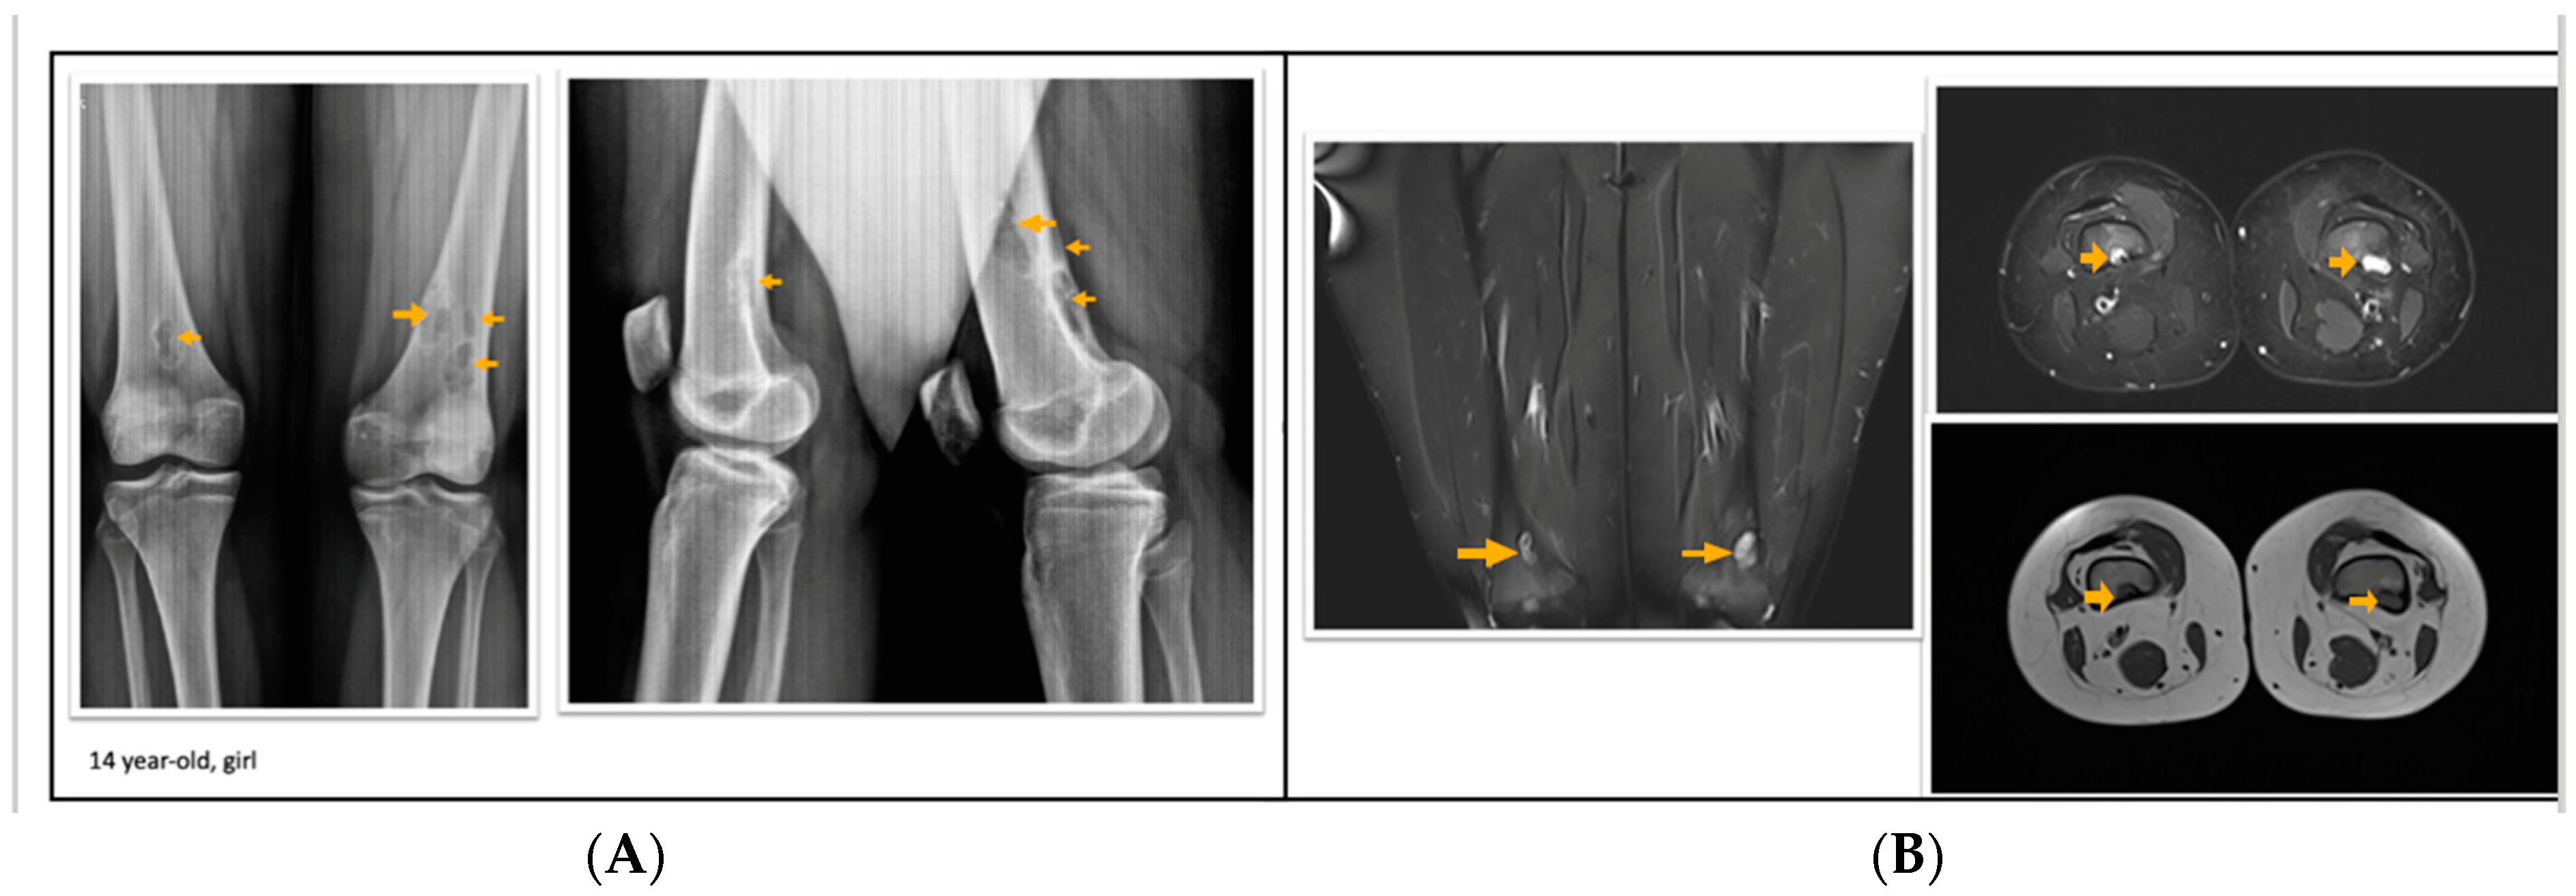

According to the radiological evaluation results, 34 lesions had X-ray scans available in the archive of the hospital. One of the patients had 3 lesions, and 2 patients had 2 lesions, while the rest had only 1 lesion, summarized as 34 lesions in 28 patients. All lesions were eccentrically located within the metaphysis of a long bone such that 22 lesions were in the femur and 12 lesions were in the tibia, 18 of the lesions were on the left side (Figure 1, Figure 2 and Figure 3). Only 4 lesions were examined with contrast-enhanced MRI; from these 3 had peripheral and only 1 had heterogeneous contrast enhancement after intravenous contrast media injection (Figure 1, Figure 2 and Figure 3).

Figure 1.

A 14-year-old girl with multiple fibrous cortical defects around the knee. (A) Direct X-ray of the knee in anteroposterior and lateral aspects show eccentrically located posteromedial and posterolateral lytic lesions with a sclerotic rim consistent with fibrous cortical defect. (B) Coronal and axial proton density and axial T1 weighted MR sections show lesions in posterior and posteromedial aspects of both femurs consistent with fibrous cortical defects. These lesions were classified as stage A according to Ritschl’s classification. Clinically, IPAQ (International Physical Activity Questionnaire): Moderately active, Screen Time: 3 h, 21-Numbered Circle VAS (21-VAS): 4.5, VAS (Visual analogue scale): 4, 21-Numbered Circle Activity Scale (21-NCAS): 6.